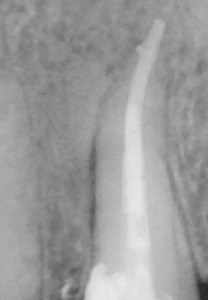

近心に全く骨が無い・・・

近心に全く骨が無い・・・

そして、すごくオーバー根充してしまった|д゚)

数か月後

数か月後